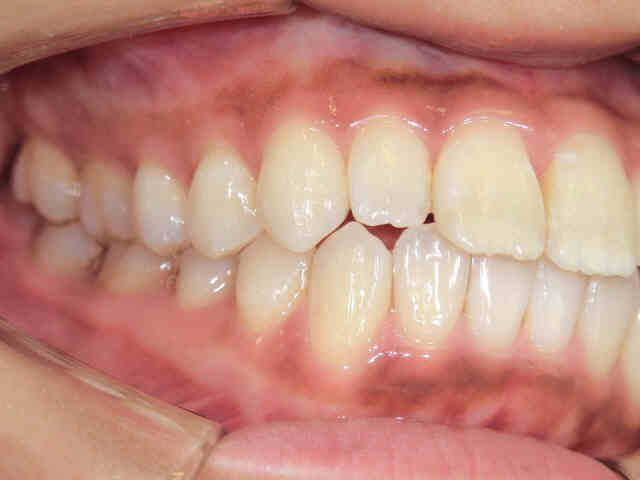

左右から見た噛み合わせの状態では、緊密な咬合が観察されます。